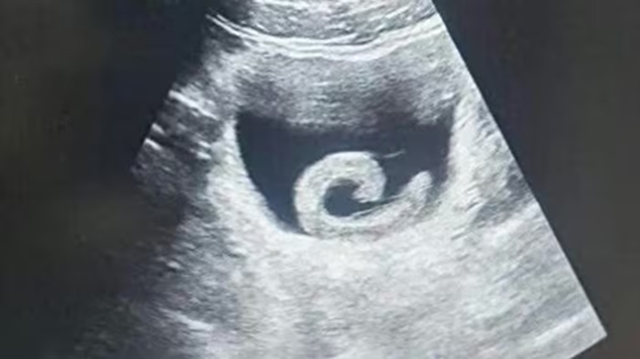

Trước khi vào viện cấp cứu Zheng đã phải chịu cơn đau dữ dội đến mức không đi nổi. Khi nghe lý do, các bác sĩ không khỏi sửng sốt. Kết quả siêu âm xác nhận đúng như anh trình bày: một con đỉa sống đang ở trong bàng quang. Ngay lập tức, các bác sĩ chuẩn bị cho ca phẫu thuật khẩn cấp nhằm loại bỏ ký sinh trùng và cứu mạng bệnh nhân.